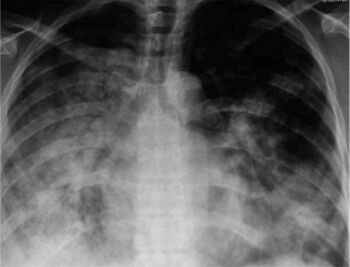

X-ray of 29-year-old person with H1N1

Diagnosis based on symptoms is fairly accurate in otherwise healthy people during seasonal epidemics and should be suspected in cases of pneumonia, acute respiratory distress syndrome (ARDS), sepsis, or if encephalitis, myocarditis, or breaking down of muscle tissue occur.[13] Because influenza is similar to other viral respiratory tract illnesses, laboratory diagnosis is necessary for confirmation. Common ways of collecting samples for testing include nasal and throat swabs.[1] Samples may be taken from the lower respiratory tract if infection has cleared the upper but not lower respiratory tract. Influenza testing is recommended for anyone hospitalized with symptoms resembling influenza during flu season or who is connected to an influenza case. For severe cases, earlier diagnosis improves patient outcome.[33] Diagnostic methods that can identify influenza include viral cultures, antibody- and antigen-detecting tests, and nucleic acid-based tests.[40]